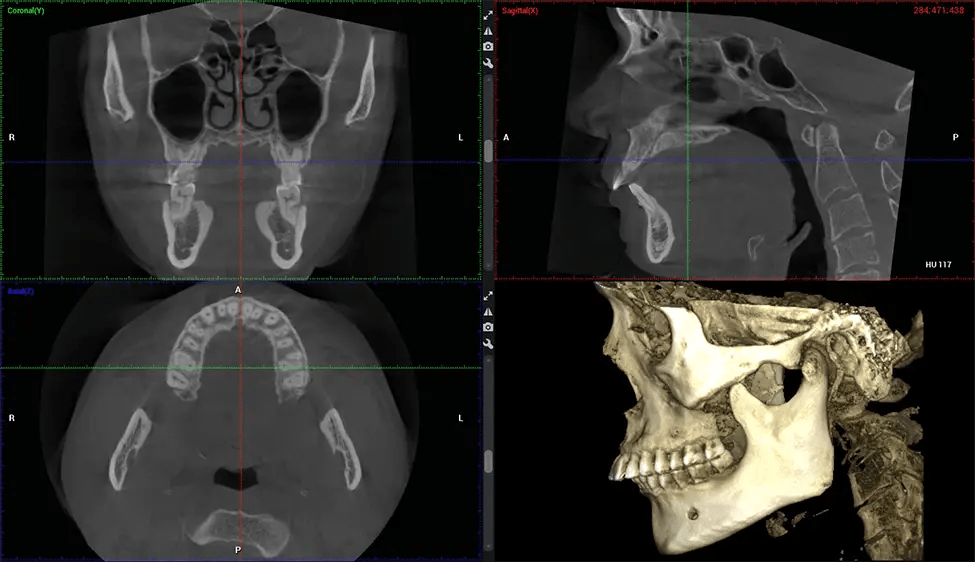

Cone Beam Computed Tomography (CBCT) is an advanced imaging technique used in dentistry and maxillofacial surgery to obtain detailed 3D images of the oral and maxillofacial structures. At Dr G Dental Studio, our CBCT scanners utilize a cone-shaped X-ray beam and a specialized detector to capture images from different angles. A computer then combines these images to create a 3D representation of the patient’s oral anatomy.

This 3D scan, called cone beam computed tomography, gives your dentist a more complete image of your oral anatomy and disease processes than a traditional X-ray. Unlike conventional X-rays, which capture a 2D image of your mouth from various angles, a 3D scan takes multiple digital X-rays for one image. It provides a complete view of your jaw, teeth, nerves, and soft tissues. This enhanced view allows dentists to detect minor issues not visible in traditional 2D scans, such as impacted wisdom teeth or bone fractures in the sinus cavity.

After the scanning process, the captured X-ray images are processed by the CBCT software, which applies algorithms to reconstruct a detailed 3D image of the scanned area. The software compiles these individual X-ray images and creates a digital 3D representation of the patient’s anatomy. The reconstructed 3D CBCT image can be viewed and analyzed by the dentist or radiologist. This image can be manipulated, rotated, and zoomed in or out to examine specific structures and evaluate the patient’s condition.

Planmeca Viso G7 CBCT ( Cone Beam CT Scan ) is designed to surpass the demands of industry leaders, specialists, and large institutions. It’s has a large ø25×30 cm sensor with four built-in cameras. It can capture unlimited volume sizes from a ø3×3 cm to a ø30x30cm volume capturing the skullcap through C7 on the cervical spine. The Planmeca Viso G7 offers the industry’s largest single volume scan of ø30×19 cm. It’s poised to handle advanced imaging modalities such as Planmeca ProFace® and Planmeca 4D™ Jaw Motion technology. The occipital head support allows an unimpeded view of facial tissue.